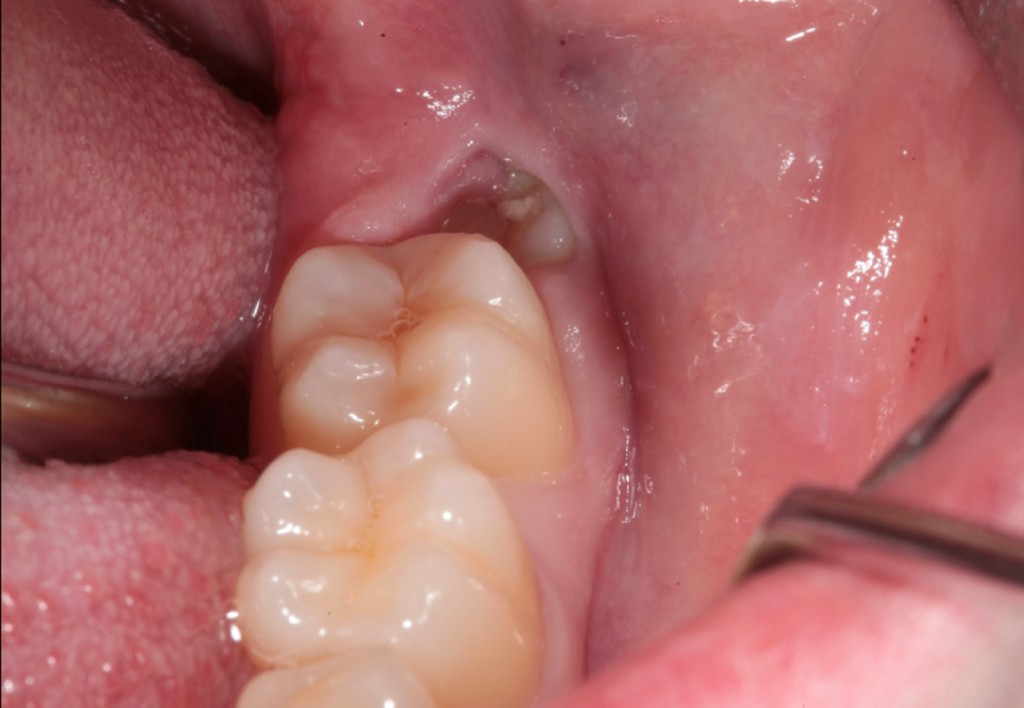

► Socket preservation

Strategie per mantenere il volume della cresta ossea e dei tessuti molli, con focus su biomateriali e tempi di guarigione.

Galleria fotografica